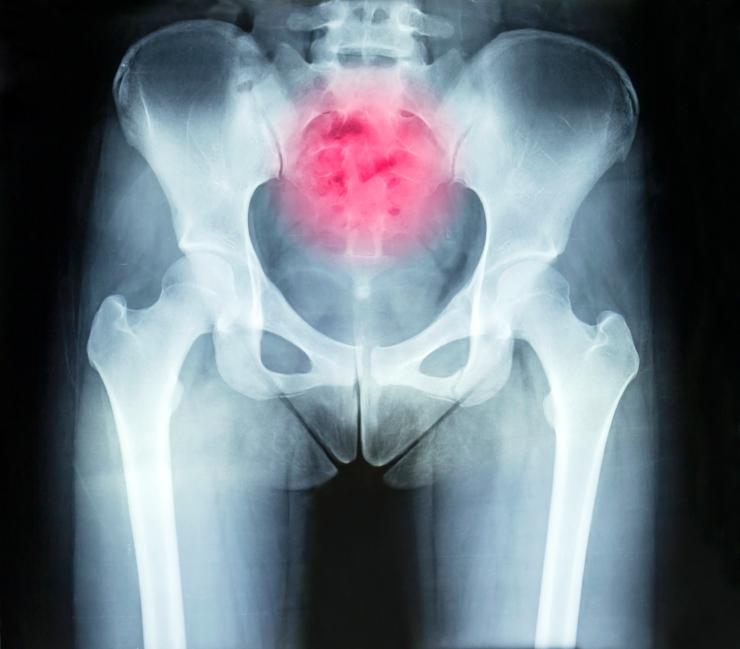

Al final de la columna vertebral se encuentra el hueso sacro, que está compuesto por cinco vértebras unidas o fusionadas y que quedan en forma de un hueso plano y ancho. A continuación del sacro, en forma de punta, está el hueso coxis o cóccix, que está formado por la unión de otras cuatro o cinco vértebras muy pequeñas, llamadas primitivas o rudimentarias. Esta parte final es una de las zonas de la columna más propensas a sufrir traumatismos y, además, es muy sensible.

Si en el primer instante tras sufrir la lesión ya notamos que es grave, por ejemplo si duele mucho o no nos podemos poner de pie, hay que ir directamente al médico. Asimismo, hay que acudir si pasadas unas horas o al día siguiente no se alivian las molestias. En el centro médico, además de la exploración física, se hará una radiografía para ver si está el coxis roto. Así, el doctor podrá diagnosticar la lesión y recomendar el mejor tratamiento según la gravedad, ya que puede ser algo muy leve o llegar incluso a provocar incapacidad.